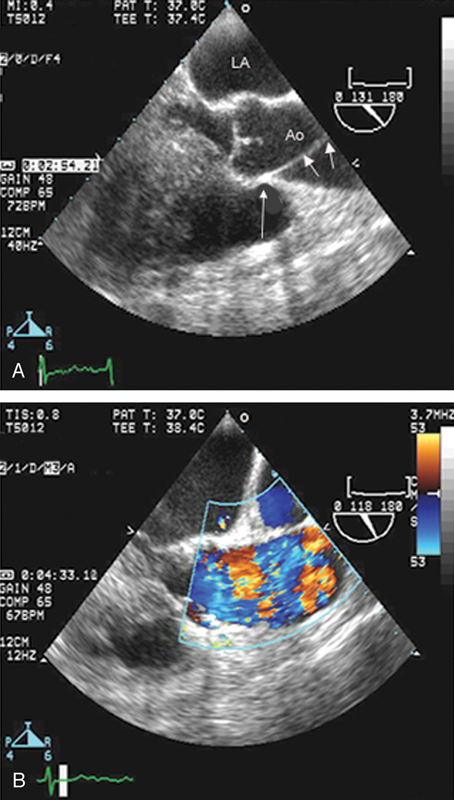

فحوصات تشخيصية لبعض امراض القلب والشرايين التاجية